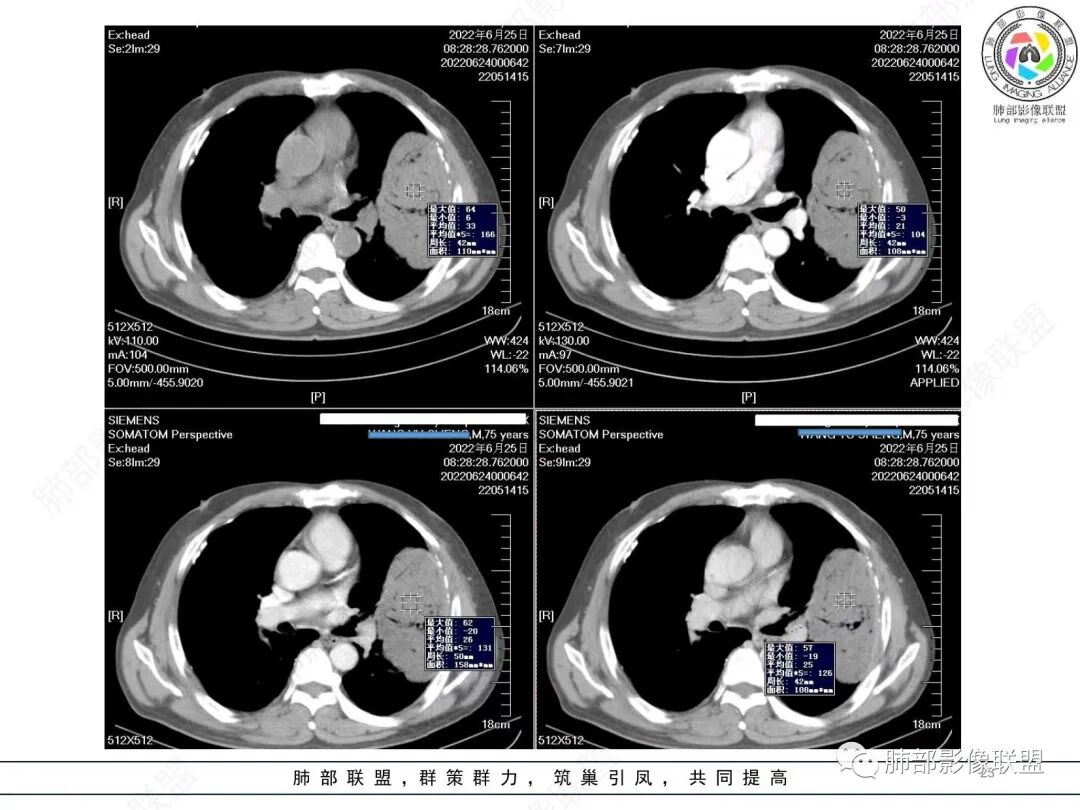

4)密度:肿块平扫为软组织密度,由于体积较大,内部常见大片状坏死,可出现不规则厚壁空洞或坏死内多发无壁小空洞,坏死多不均匀:坏死灶内可见如柳絮样的斑片样强化灶,坏死边缘与非坏死区分界不清本例坏死较明显,密度不均匀。

5)肿瘤强化方式:肺部恶性肿瘤强化程度与其血供丰富程度相关,血供丰富多强化明显,反之则较差。由于PSC 周边实性部分富血供及内部黏液变性、坏死,增强后肿块多数呈轻-中度边缘环形强化或不均匀小斑片状强化。国外学者对照病理发现肿瘤细胞或胶原组织增强扫描时强化,无强化的低密度区代表了黏液样变性区和出血坏死区。